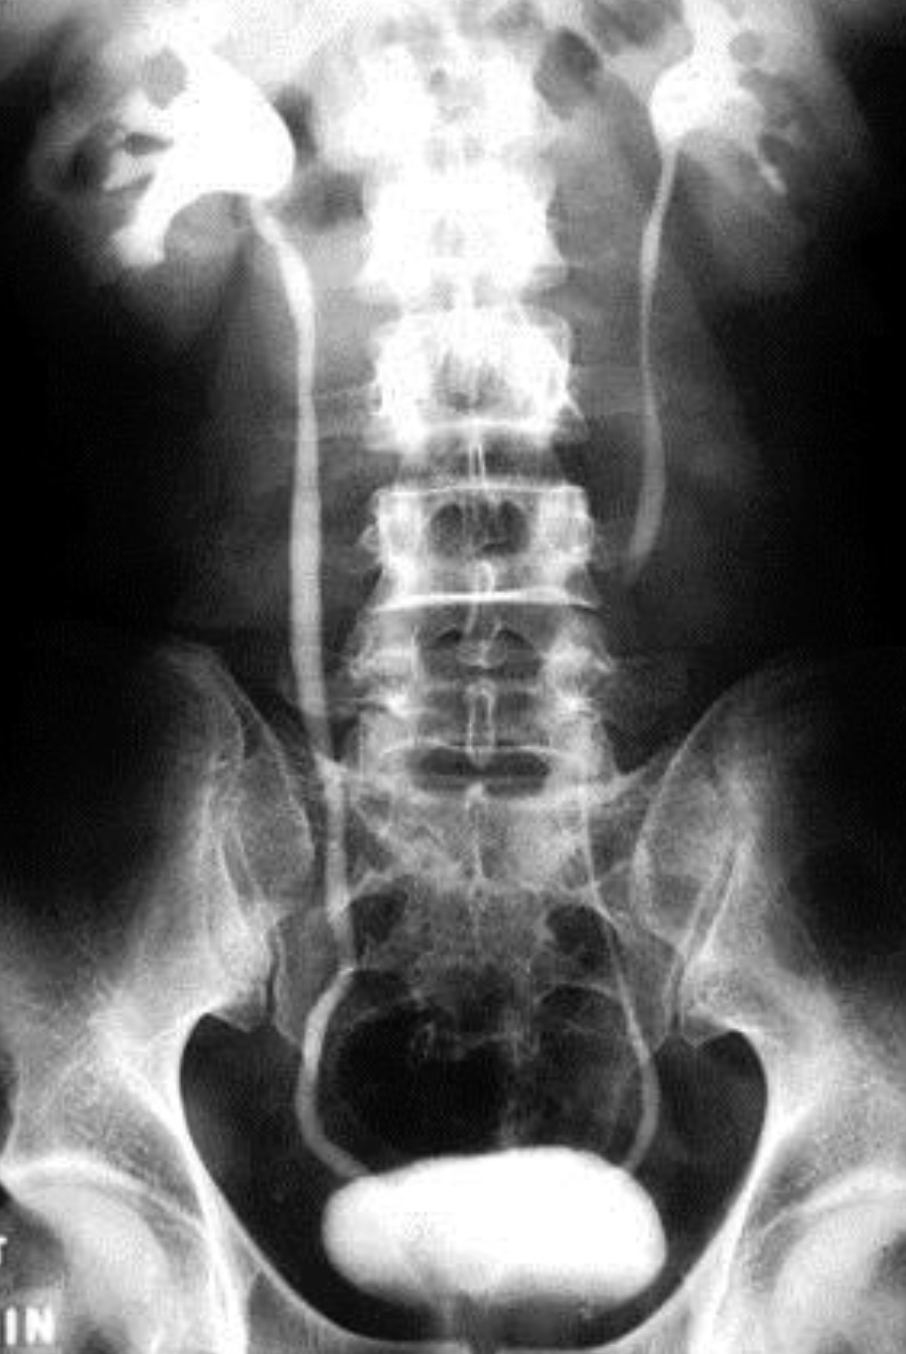

IMAGING: i.v.Pyelogram, u/s, CT (with contrast)

i.v. pyelogram (I.V.P)

Role of Imaging

Plain x-ray

Intravenous pyelography (IVP)